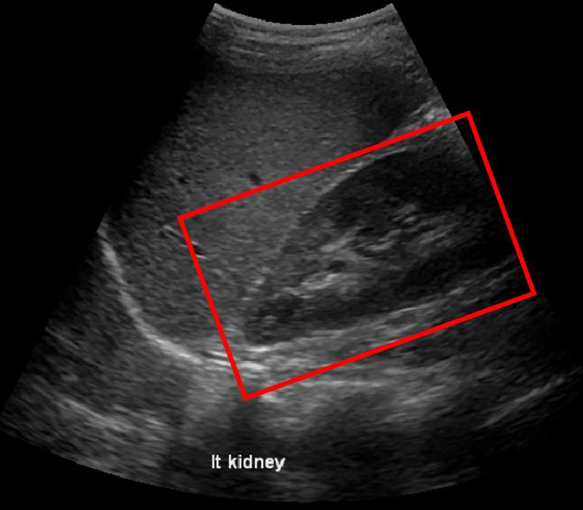

Fig. 3LABEL:sub@subfig:a and LABEL:sub@subfig:b shows a case in which the baseline method was affected by the presence of diaphragm, kidney and liver boundaries creating a texture similar to renal-sinus portion, while CaffeNet had excellent localization. Fig. 3LABEL:sub@subfig:c and LABEL:sub@subfig:d illustrate a case where CaffeNet resulted in over-segmentation containing the diaphragm, clearly illustrating that in limited data problems careful feature-engineering incorporating domain knowledge still carries a lot of relevance. Finally, we achieved a best performance of 86% average detection accuracy using the hybrid approach (Section 3.5). More importantly, the number of failures of the hybrid approach was 3/45, which is 20% better than either of the methods.

(a) Haar

(b) CaffeNet_FA

(c) Haar

(d) CaffeNet_FA

Figure 3: Visual comparison of Baseline Method with CaffeNet Transfer